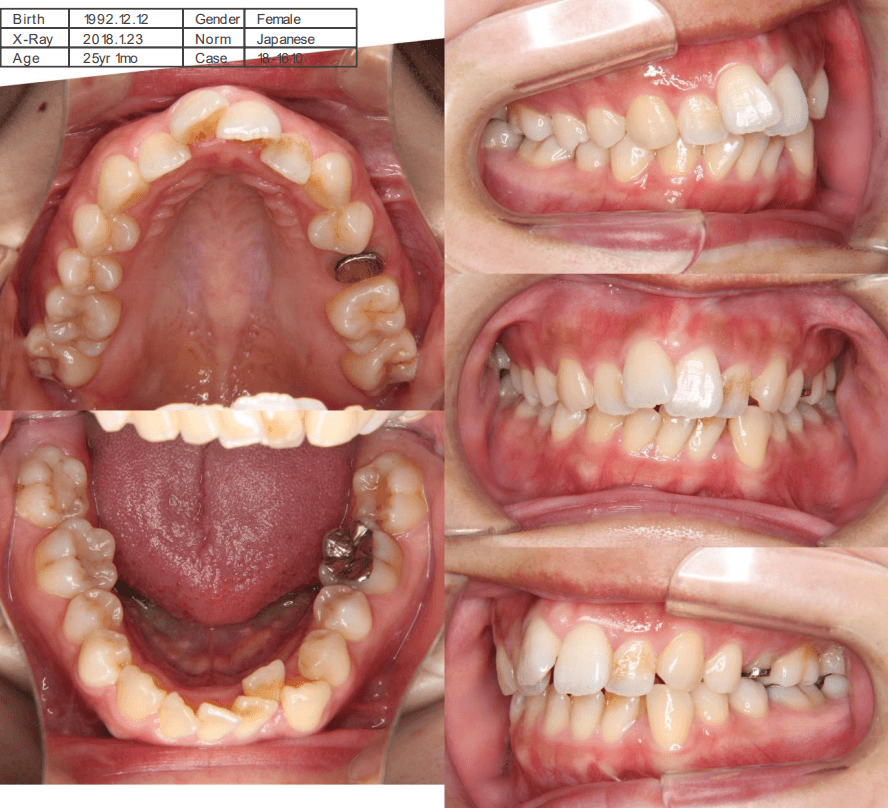

| 年齢・性別 | 25歳女性 |

|---|---|

| 主訴 | 前歯の歯並びの乱れ(叢生)を気にされて来院された。咬み合わせや審美的な改善を希望されていました。 |

| 治療期間・回数 | 4年5ヶ月・30回 |

| 費用 | 1100,000円(税別) |